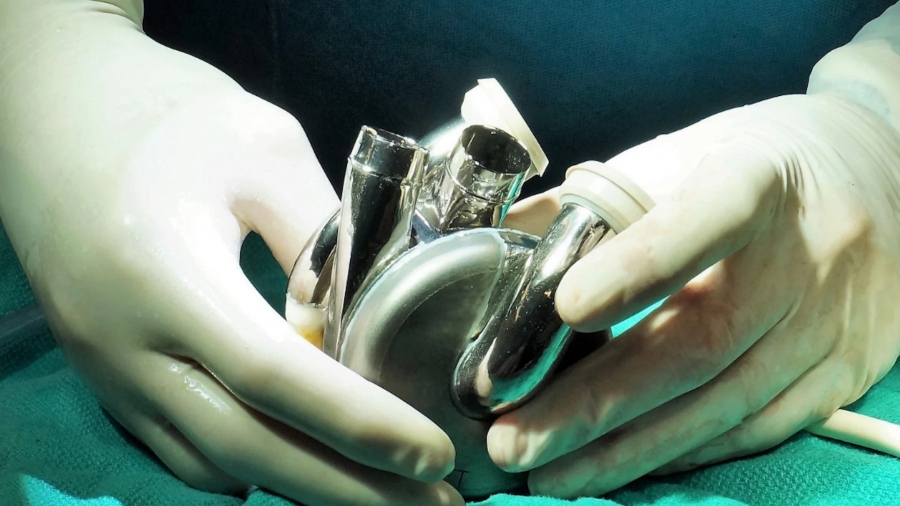

Ένας Αυστραλός ερευνητής, ο Daniel Timms, με τη βοήθεια του πατέρα του, ανέπτυξε στην κουζίνα του σπιτιού του την πρώτη πλήρως τεχνητή καρδιά από τιτάνιο – μια συσκευή που μπορεί να αντικαταστήσει ολοκληρωτικά τις παραδοσιακές μεταμοσχεύσεις.

Το δίδυμο πατέρας-γιου εργάστηκε ακούραστα στο οικογενειακό τους σπίτι στο Μπρίσμπεϊν της Αυστραλίας για να κατασκευάσουν ένα πρωτότυπο που τελικά εξελίχθηκε στην πρώτη ανθεκτική τεχνητή καρδιά – μια μηχανική αντλία αίματος από τιτάνιο.

Η συσκευή, κατασκευασμένη από την εταιρεία του Timms, BiVACOR, με το μοναδικό μέταλλο που δεν απορρίπτεται από τον ανθρώπινο οργανισμό, έγινε παγκοσμίως γνωστή τον προηγούμενο μήνα όταν αποκαλύφθηκε πως ένας ασθενής στο Σίδνεϊ έγινε ο πρώτος άνθρωπος στον κόσμο που πήρε εξιτήριο από νοσοκομείο με τη συσκευή εμφυτευμένη.

Ο ίδιος ο Timms είναι παρών στις επεμβάσεις, παρακολουθώντας με αγωνία την τοποθέτηση της συσκευής σε κάθε ασθενή.

Το δίδυμο πατέρας-γιου εργάστηκε ακούραστα στο οικογενειακό τους σπίτι στο Μπρίσμπεϊν της Αυστραλίας για να κατασκευάσουν ένα πρωτότυπο που τελικά εξελίχθηκε στην πρώτη ανθεκτική τεχνητή καρδιά – μια μηχανική αντλία αίματος από τιτάνιο.

Η συσκευή, κατασκευασμένη από την εταιρεία του Timms, BiVACOR, με το μοναδικό μέταλλο που δεν απορρίπτεται από τον ανθρώπινο οργανισμό, έγινε παγκοσμίως γνωστή τον προηγούμενο μήνα όταν αποκαλύφθηκε πως ένας ασθενής στο Σίδνεϊ έγινε ο πρώτος άνθρωπος στον κόσμο που πήρε εξιτήριο από νοσοκομείο με τη συσκευή εμφυτευμένη.

Ο ίδιος ο Timms είναι παρών στις επεμβάσεις, παρακολουθώντας με αγωνία την τοποθέτηση της συσκευής σε κάθε ασθενή.